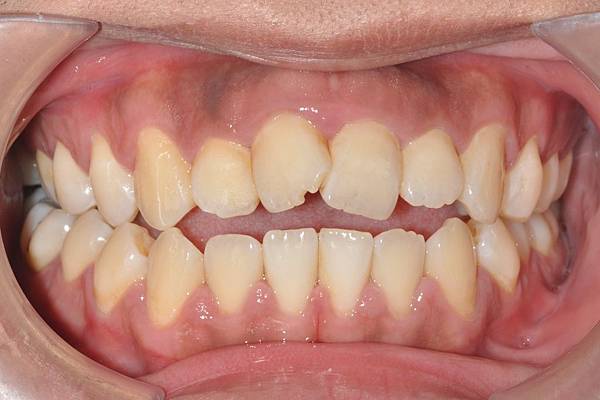

網紅林進藉由矯正改善臉型達到整形效果

拔牙合併微骨釘

本來就很愛笑的林進,藉由“

”

將前牙後退嘴脣後縮,並藉由齒列上壓作下顎逆時針旋轉,達到接近整形墊下巴的效果!!

治療前/治療後

-以上案例由林昇進醫師提供